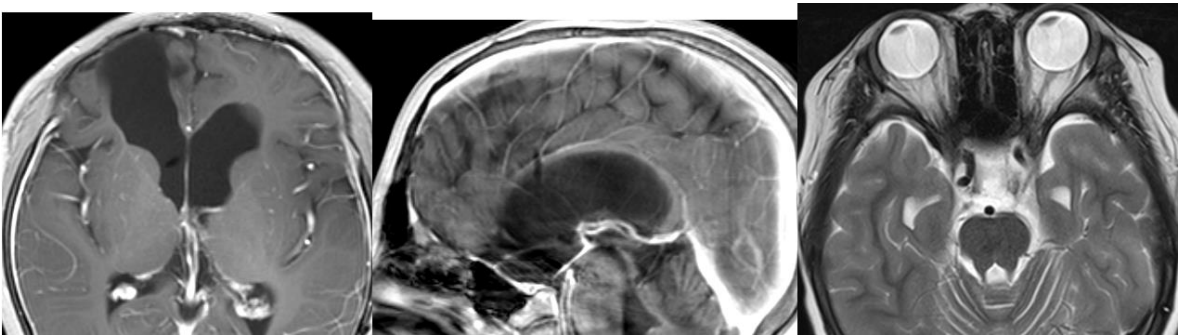

核磁影像顯示腫瘤全切并沒有復發(fā),視力較前明顯好轉(zhuǎn),無其他神經(jīng)功能新癥狀。對于小冬3年來的康復進展,巴教授表示欣慰。以下為術(shù)后3年半的MRI影像。